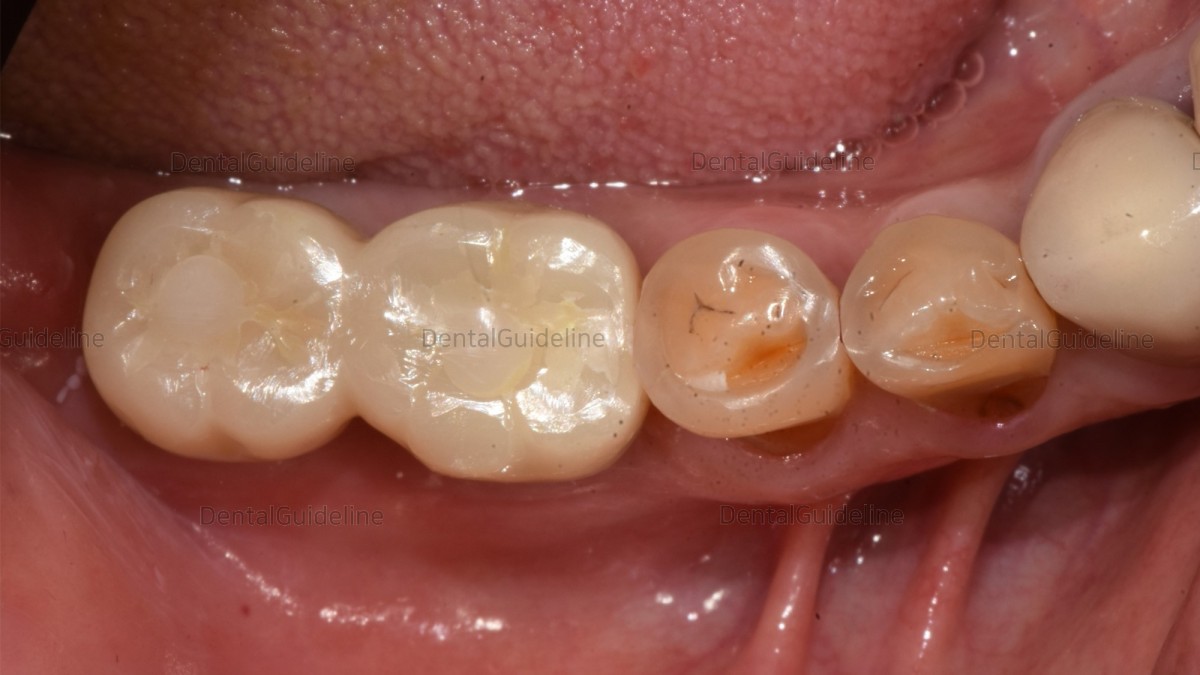

occlusal and contact point adjustment.

Permanent cementation and access hole filling with resin.